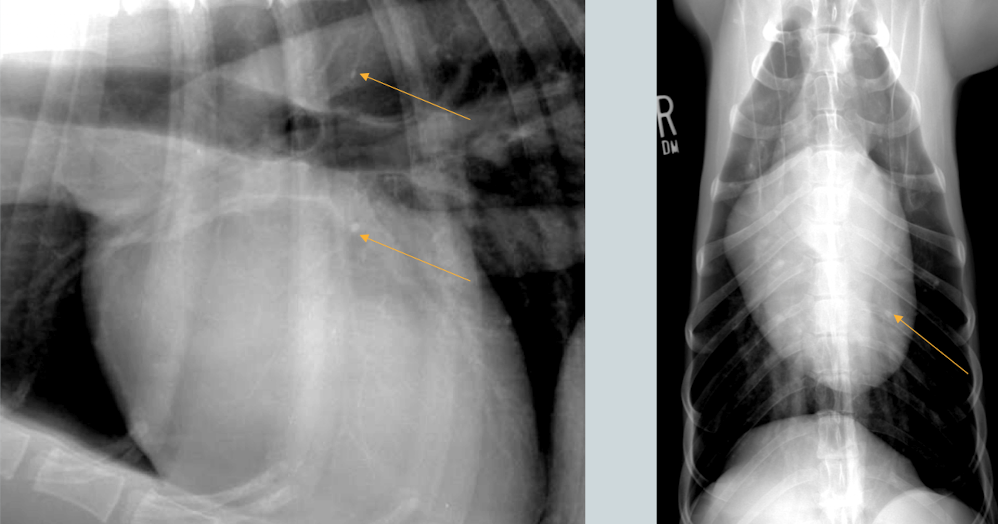

Wha condition is this image depicting? What is the red label showing?

Shoulder DJD

Osteophytes present on the caudal glenoid cavity and caudal humeral head

What is the general condition depicted?

What are the numbers labelling?

Hip DJD

acetabular rim osteophytes

femoral head osteophytes

morgan line (poor example)

subchondral sclerosis of acetabular rim

What condition? What main feature does the image show?

Stifle DJD (likely from a cruciate ligament rupture)

intracapsular swelling (cranial displacement of infra patellar fat pad and caudal displacement of fascial stripe)